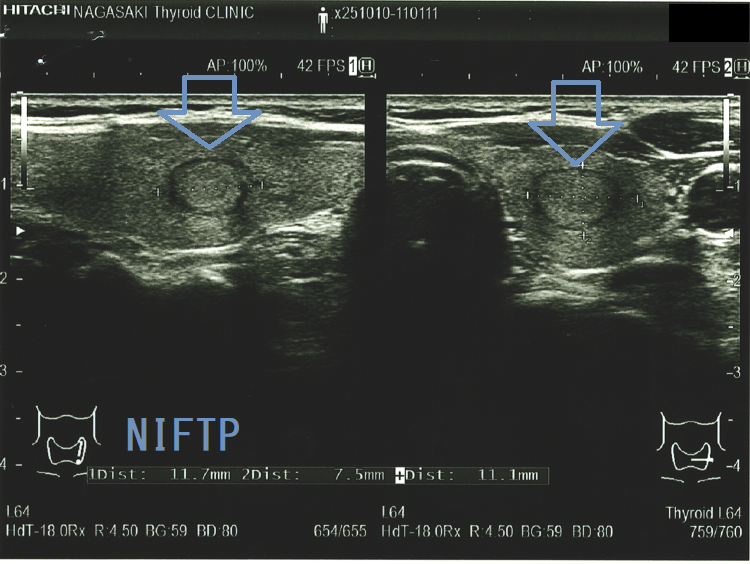

Non-invasive follicular thyroid neoplasm with papillary-like nuclear features (NIFTP) 超音波(エコー)画像;見かけは濾胞型甲状腺乳頭癌、 濾胞性腫瘍、腺腫様結節と鑑別できまない

Non-invasive follicular thyroid neoplasm with papillary-like nuclear features (NIFTP) 超音波(エコー)画像 (水平断)

Non-invasive follicular thyroid neoplasm with papillary-like nuclear features (NIFTP)の超音波(エコー)所見は、

- 被膜が存在(被膜のない場合もある)

- 充実性、等エコーが多い

- 砂粒状石灰化を認めない

などで、濾胞型甲状腺乳頭癌、濾胞性腫瘍(良性濾胞腺腫 、甲状腺濾胞癌)と鑑別できません。砂粒状石灰化のない濾胞型甲状腺乳頭癌なんて普通に存在します。NIFTPの60.1%は悪性を疑う所見が無いとされます[Endocrine. 2021 Jul;73(1):131-140.]。